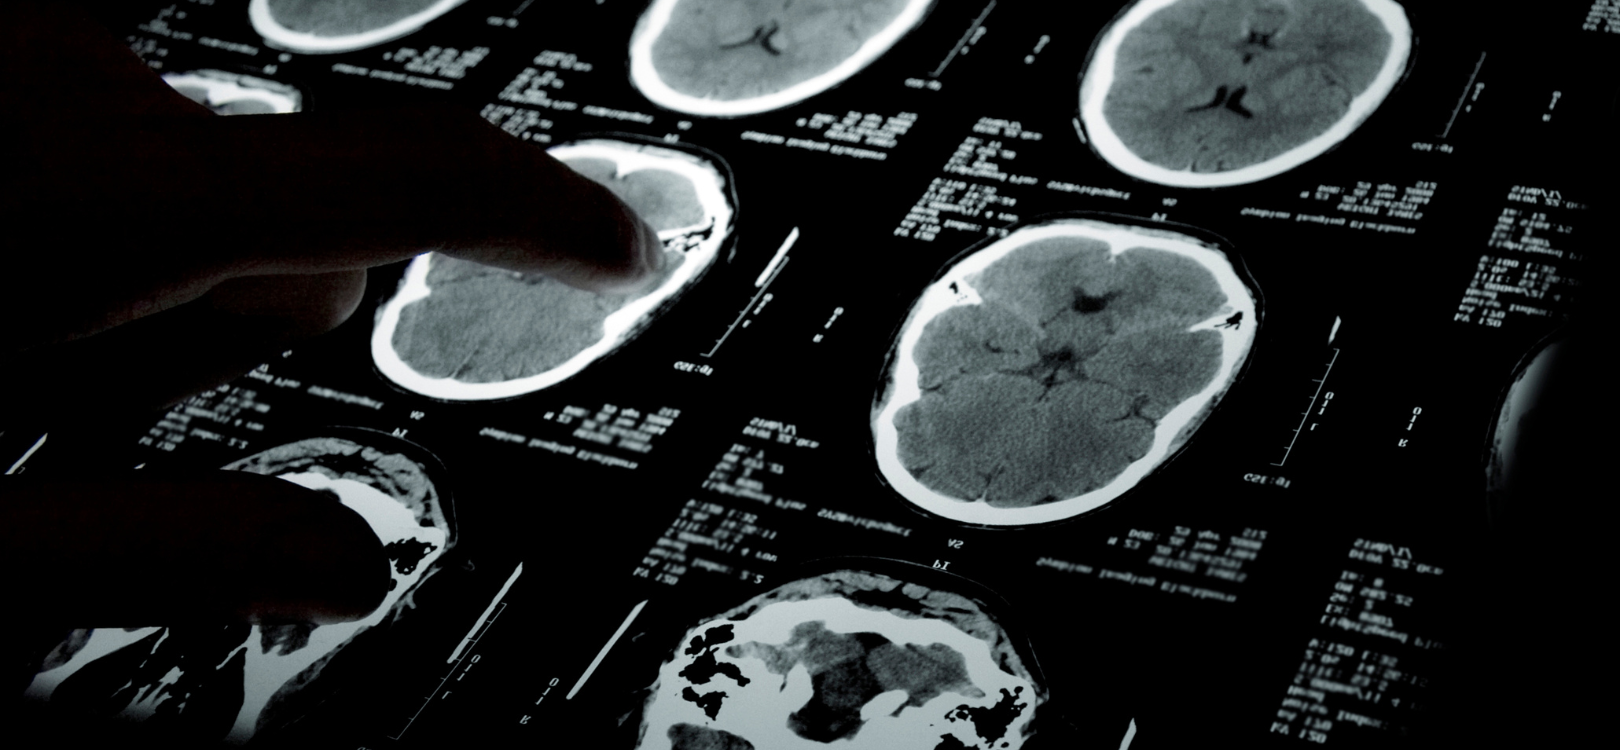

Neuropsychiatric disorders are complex conditions that arise from the interface of neurology and psychiatry. These disorders affect both brain function and mental health—often causing cognitive disturbances, mood instability, behavioral changes, and in some cases, motor or neurological symptoms. At La Mente – The Mind Clinic, we specialize in the accurate diagnosis and integrated treatment of such conditions in our branches across  KPHB, Narsingi, and Attapur.

Diagnosis involves a combination of clinical evaluation, neurological tests (like EEG or MRI), and psychological assessments to understand cognitive, emotional, and behavioral patterns.